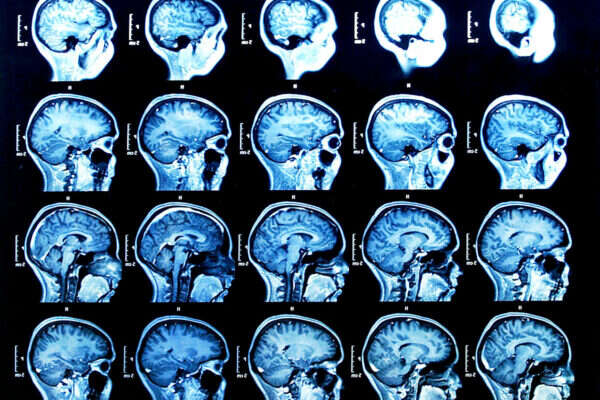

אומרים שהמוח הוא האיבר הכי חיוני בגוף האדם. האומנם? כולנו הולכים מבקרים מידי פעם אצל הרופא בכדי לטפל במחלות שונות שתוקפות אותנו. אבל חולה אחד בצרפת קיבל את השוק של חייו כאשר הלך לטפל בכאבים ברגלו – הרופאים הודיעו לו כי חסר לו חצי מוח.

ליאוניל פוילנט, שחקר את מוחו של האיש לאחר הגילוי המדהים, ציין בכת העת הרפואי: "כל המוח שלו הצטמצם - האונות הקדמיות, הקודקודית, הזמניות והעורפיות – בשני הצדדים גם בימין וגם בשמאל. האזורים הללו במוח שולטים על תנועה, רגישויות, שפה, ראייה, רגשות ופונקציות קוגנטיביות נוספות."

הרופאים הסבירו כי התופעה היא הפרעה שלאחר הלידה, שנגרמה ממים בתוך המוח. עם השנים הצטמצם מוחו של הצרפתי ב-50%-75%. כעת, שמונה שנים לאחר הגילוי והטיפול שניתן לו, מאמינים הרופאים כי הוא ניצל מכיוון שמוחו ארגן את עצמו מחדש. רוב הנוזלים שנאגרו במוחו נעלמו וכיום חי האיש באופן נורמאלי.

חוקרים, שכותבים בכתב העת בו פורסם המקרה, הגיעו לכדי מסקנה שהאינטליגנציה של אדם לא בהכרח קשורה לגודל של המוח, לפחות לא כמו שחשבו עד היום. הם מאמינים שההסבר לכך הוא שהחלקים המעטים של מוחו שנותרו, "עשו את העבודה" של החסרים. אז אולי בכל זאת הגודל לא קובע?